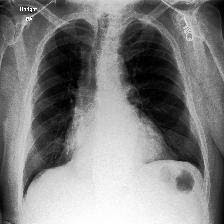

Disease classification relying solely on imaging data attracts great interest in medical image analysis. Current models could be further improved, however, by also employing Electronic Health Records (EHRs), which contain rich information on patients and findings from clinicians. It is challenging to incorporate this information into disease classification due to the high reliance on clinician input in EHRs, limiting the possibility for automated diagnosis. In this paper, we propose \textit{variational knowledge distillation} (VKD), which is a new probabilistic inference framework for disease classification based on X-rays that leverages knowledge from EHRs. Specifically, we introduce a conditional latent variable model, where we infer the latent representation of the X-ray image with the variational posterior conditioning on the associated EHR text. By doing so, the model acquires the ability to extract the visual features relevant to the disease during learning and can therefore perform more accurate classification for unseen patients at inference based solely on their X-ray scans. We demonstrate the effectiveness of our method on three public benchmark datasets with paired X-ray images and EHRs. The results show that the proposed variational knowledge distillation can consistently improve the performance of medical image classification and significantly surpasses current methods.

翻译:仅依靠成像数据的疾病分类吸引了对医学图像分析的极大兴趣。但是,目前的模型还可以通过采用包含关于病人和临床医生发现情况的丰富信息的电子健康记录(EHRs)来进一步改进。由于在EHRs中高度依赖临床投入,因此将这一信息纳入疾病分类具有挑战性,限制了自动诊断的可能性。在本文件中,我们提议了\textit{ varitional point squining} (VKD),这是基于X光的疾病分类的一个新的概率推论框架,它利用了EHRs的知识。具体地说,我们采用了一个有条件的潜伏变异模型,我们通过该模型将X光图像与相关EHR文本的变异后视镜调节条件的潜在的X射线图像的显示纳入疾病分类。通过这样做,模型获得了在学习期间提取与该疾病相关的视觉特征的能力,因此能够仅仅根据X光扫描结果对隐蔽病人进行更精确的推断。我们用三个公共基准数据集与配对X光图像和EHRs 的模拟方法证明了我们的方法的有效性。我们采用了一个有条件的隐隐隐隐隐隐性潜变量,从而能够持续地改进目前医学图像的成绩。结果,从而显示了拟议的变异性。